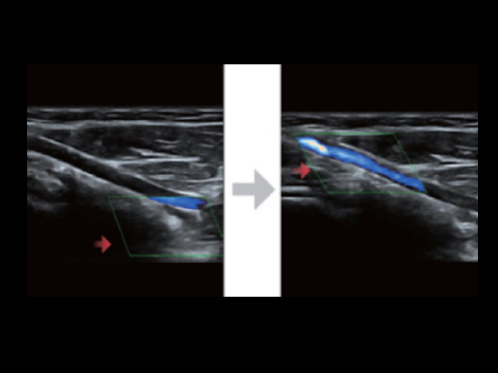

eXpress Clarity

More clarity at hand